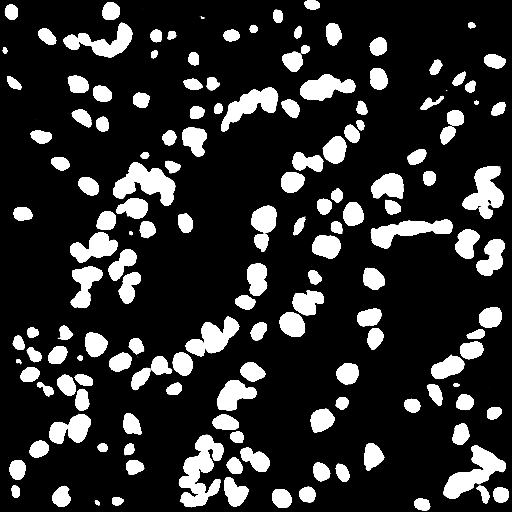

Refer to caption

Figure 3: Visualization of the segmented cells and the generated graphs from an arbitrary patch sample of GIST-PDL1. The four subgraphs from left to right are the raw patch image, the segmented cells masks, the patch image with overlaid segmentation masks, and the generated graph.

To better understand the learned graphs that are generated from histology images, Figures 3-8 investigate some random patch images from the three datasets and visualize the nuclei segmentation results and the associated graphs. In particular, the four subgraphs from left to right of each figure display the raw patch image, the segmented cells masks, the patch image with overlaid segmentation masks, and the generated graph.